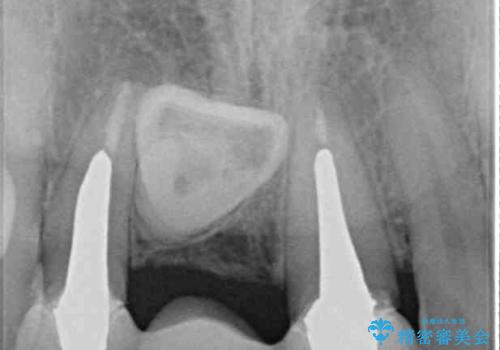

前院では、土台の金属を除去することは不可能であると言われたとのことでした。金属の土台が残っているとセラミックにグレーの金属色が透けて見えてしまうため、拡大鏡やマイクロスコープを用いて丁寧に除去し、天然歯の色に近いファイバーコアを植立することとしました。

また、歯とクラウンの境目が合っていない部分が多く、歯肉からの出血が認められました。